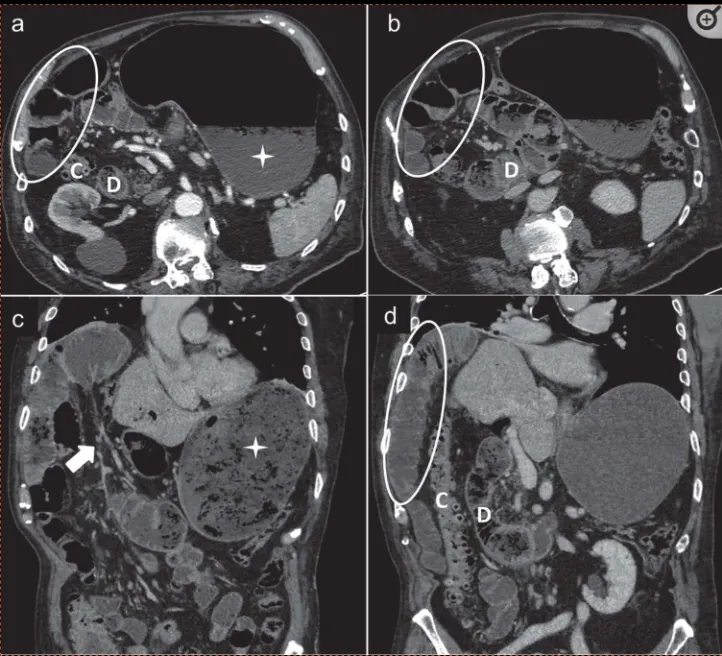

a,b : 소장 loop가 복부 전벽에 인접하여 있다. SMV의 직경이 좁아져 beaked 모양으로 보인다 (화살촉)

herniated mesenteric loop 가 버섯 모양처럼 보인다.

(3) Surrounding viscera

Small-bowel behind superior mesenteric artery

Abnormal position of the jejuno-jejunostomy